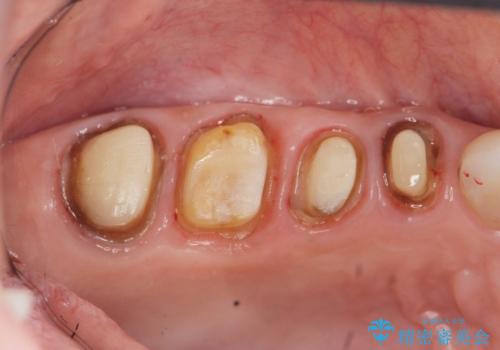

臼歯部メタルフリー再補綴

- 治療してからの年月が経過し、かみにくくなったブリッジ・クラウンを全てやりかえたいと希望され来院されました。

クラウン・ブリッジを作り替えるにあたり虫歯の徹底的な除去・根管治療のやり直しを行い今後やり直しをしなくて済むような環境を整えていきます。

装着して長期間経過したブリッジやクラウンは隙間から細菌が侵入し虫歯が再発してしまっていることがあります。

長期的に問題のないブリッジ・クラウンを作製するため、虫歯をしっかりと除去すること精密な根管治療を行うことが肝要です。